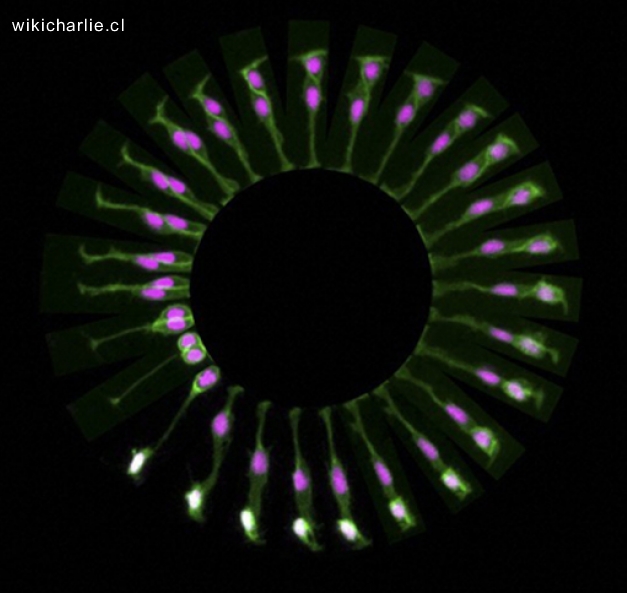

Modelo de alta resolución del patrón de activación de los genes en el cerebro humano

Un equipo del Instituto Allen, liderado por Ed Lein ha generado un modelo de alta resolución del patrón de activación de los genes en el cerebro humano durante el desarrollo embrionario, concretamente en las semanas 15, 16 y 21 de gestación. «Conocer cuándo un gen se expresa en el cerebro puede dar pistas importantes acerca de su función», explica Ed Lein, investigador en el Instituto Allen para la Ciencia del Cerebro.

Instrucciones

«Este atlas ofrece una visión completa de qué genes están activos en un momento determinado, en una región concreta y en qué tipos de células, durante el desarrollo embrionario. Esto significa que tenemos un mapa del cerebro humano en desarrollo. Algo crucial para entender cómo se forma el cerebro de manera saludable y una poderosa herramienta para investigar que va mal en la enfermedad», explica Lein.

Lo que han conseguido los investigadores del Allen «es una especie de manual de instrucciones de cómo se va formando el cerebro, limitado a tres estadíos del desarrollo embrionario, aunque con datos de miles de genes». Esta es la primera vez que se obtiene un mapa de expresión génica de este tipo en humanos.

En especial, resaltan los autores, el trabajo puede aportar datos muy interesantes en patologías como el autismo, que se empiezan a gestar durante el desarrollo embrionario. «En patologías como el autismo o la esquizofrenia hay alteraciones muy sutiles en la arquitectura cerebral, debido a la expresión de distintos genes».

Conocer dónde y cuándo se activan los distintos genes que intervienen en el desarrollo del cerebro es importante también a la hora de desarrollar posibles dianas terapuéticas, que destaca el enorme valor de este trabajo para la comunidad científica.